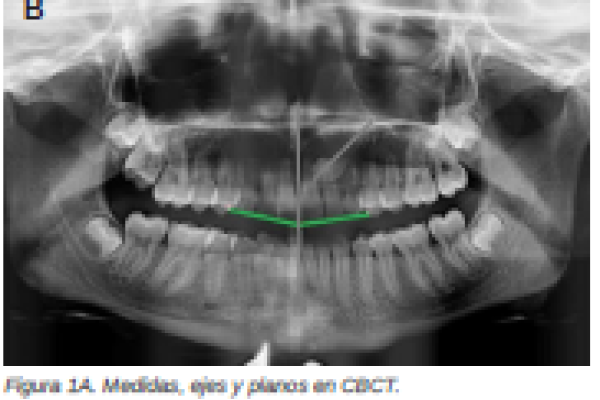

Retención de segundos molares mandibulares: evaluación mediante CBCT y consideraciones terapéuticas ante un caso clínico